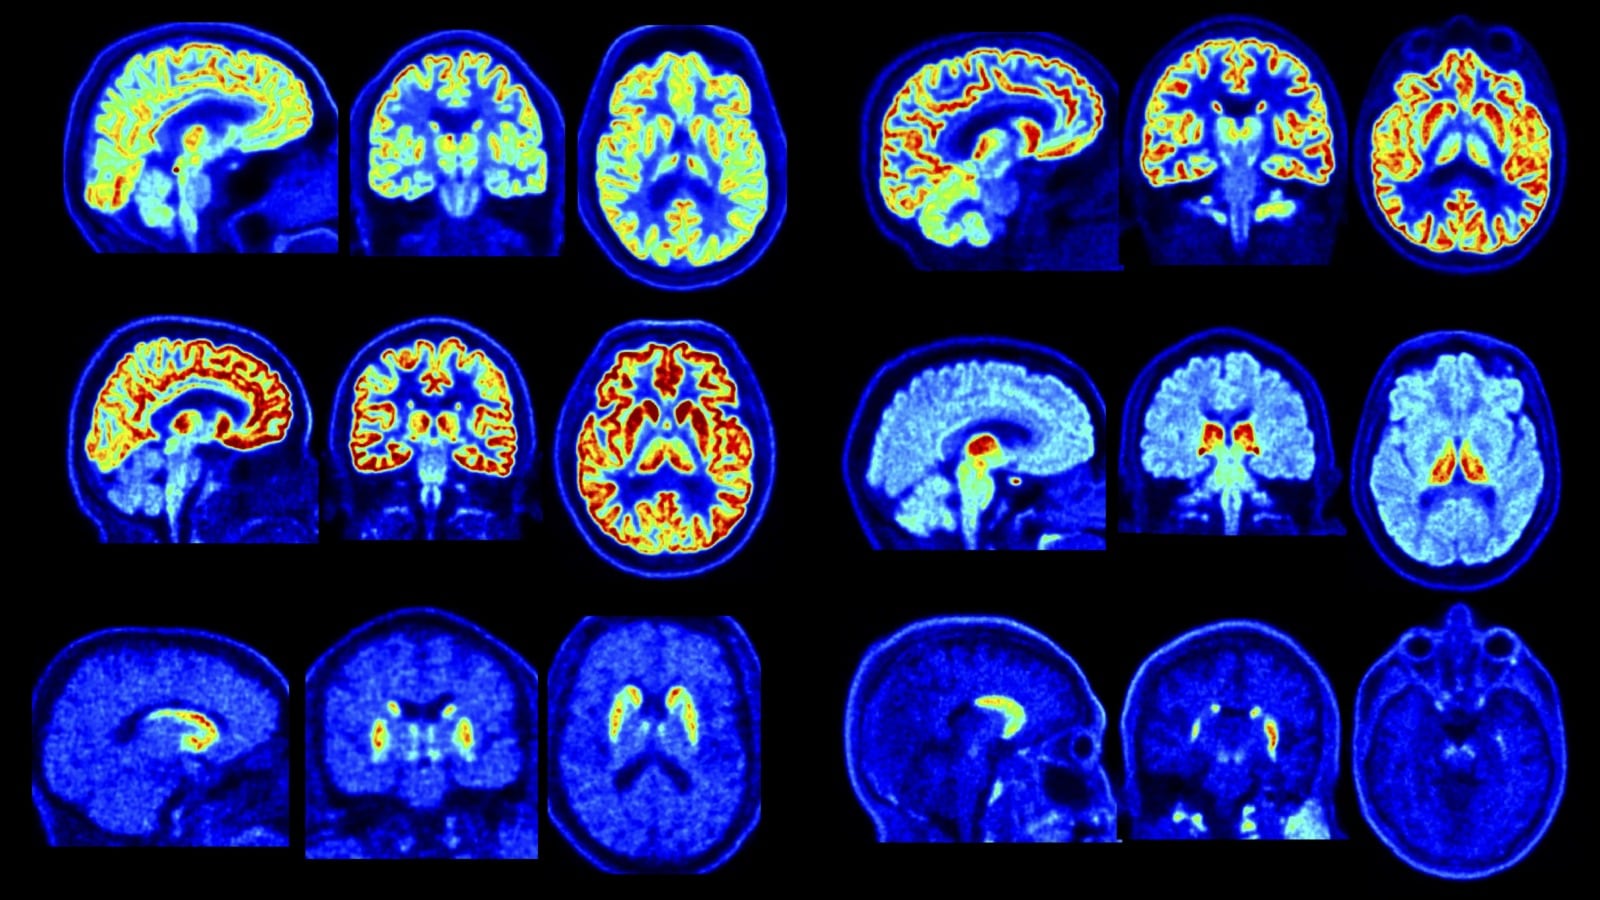

Un equipo de investigadores de la Universidad de Yale dio a conocer los primeros resultados de las pruebas realizadas con NeuroEXPLORER, un escáner cerebral de última generación que promete cambiar la forma de estudiar el cerebro humano. El dispositivo, que ya opera en el PET Center de la universidad, en New Haven (Estados Unidos), ofrece imágenes de una nitidez inédita para la investigación neurológica.

Gracias a esta tecnología, médicos y científicos podrán detectar señales de enfermedades en etapas mucho más tempranas y comprender con mayor precisión cómo interactúan y funcionan las distintas áreas cerebrales. El avance abre la puerta a estudios que hasta ahora eran técnicamente imposibles, marcando un salto clave en el diagnóstico y la investigación del sistema nervioso.

El nuevo escáner destaca porque capta señales más pequeñas, ve mejor las estructuras profundas y muestra cómo trabajan distintas partes del cerebro. Además, puede distinguir entre problemas diferentes, como tumores o daños por enfermedades como el Alzheimer y el Parkinson.

Según Tommaso Volpi, otro de los investigadores, el grupo estudió los cerebros de siete personas usando siete tipos de sustancias distintas con el escáner. Así pudieron ver claramente partes difíciles de detectar, como el tracto mamilotalámico y la sustancia negra, dos zonas clave para la memoria, el movimiento y enfermedades como el Parkinson.